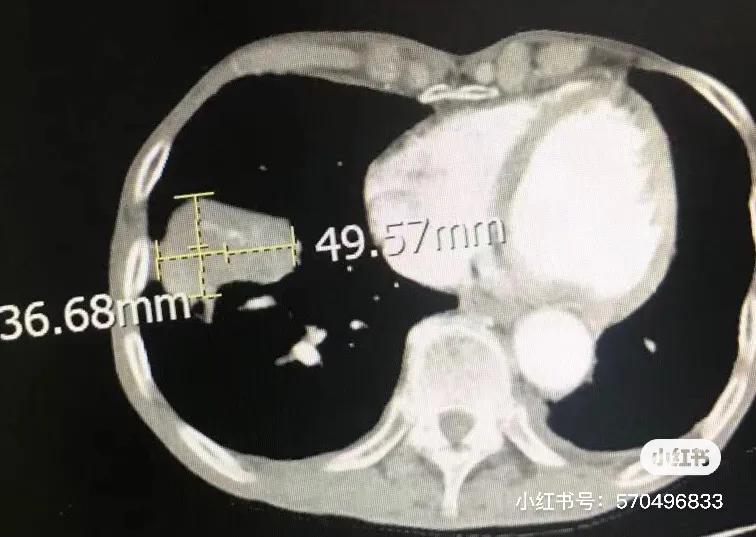

第一次冷冻后一个月CT